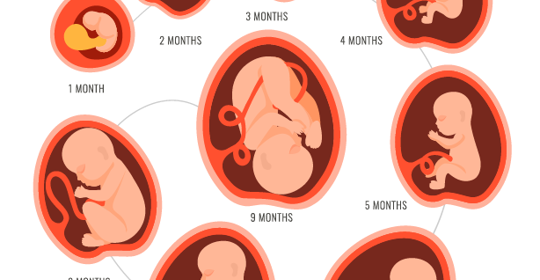

孕:37周後胎兒體重增加範圍與16周輕微腹痛與胎動

本文介紹了孕37周後胎兒體重還會增加多少以及孕16周肚子偶爾輕微疼是否為胎動的問題。孕37周後胎兒體重還會增加多少在臨床上並沒有明確的參考範圍;而孕16周肚子偶爾輕微疼可能與胎動有關,但具體還需結合其他症狀進行分析。若擔心胎兒健康或疼痛加劇,建議及時就醫進行檢查。